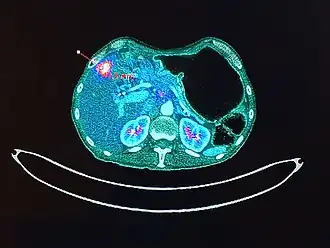

La imagen se obtiene gracias a que los tomógrafos son capaces de detectar estos fotones gamma emitidos por el paciente. Para que estos fotones acaben por conformar la imagen deben detectarse ¨en coincidencia¨, es decir, al mismo tiempo; en una ventana de tiempo adecuada (nanosegundos), y además deben provenir de la misma dirección y sentidos opuestos. Además su energía debe superar un umbral mínimo que certifique que no ha sufrido dispersiones energéticas de importancia en su trayecto (fenómeno de scatter) hasta los detectores. Esta captación permite deducir que el radioisótopo se encuentra en la línea que une los detectores diametralmente opuestos. Esta línea que une ambos detectores recibe el nombre de línea de respuesta (LOR). La ventana de coincidencia depende directamente de la capacidad del cristal detector para producir luz. Gracias a la simetría axial de los detectores, el almacenamiento de los datos en el equipo PET se simplifica. Cada adquisición se registra sobre la base de sus coordenadas polares (r, θ) y a esta representación se le denomina sinograma. Además, al finalizar la adquisición han quedado registradas el número de aniquilaciones en cada dirección, lo que permite asignar a la imagen final distintas intensidades en función de la concentración del radiofármaco. Estos sinogramas son similares a las proyecciones capturadas por un tomógrafo de CT. Sin embargo, el número de eventos registrados durante la adquisición es mucho menor en el caso de PET por lo que las imágenes aparecen más ruidosas.

Así, la PET nos permite estimar los focos de crecimiento celular anormal en todo el organismo, en un solo estudio, por ser un estudio de cuerpo entero, por lo tanto nos permitirá conocer la extensión. Pero además sirve, entre otras cosas, para evaluar en estudios de control la respuesta al tratamiento, al comparar el comportamiento del metabolismo en las zonas de interés entre los dos estudios.